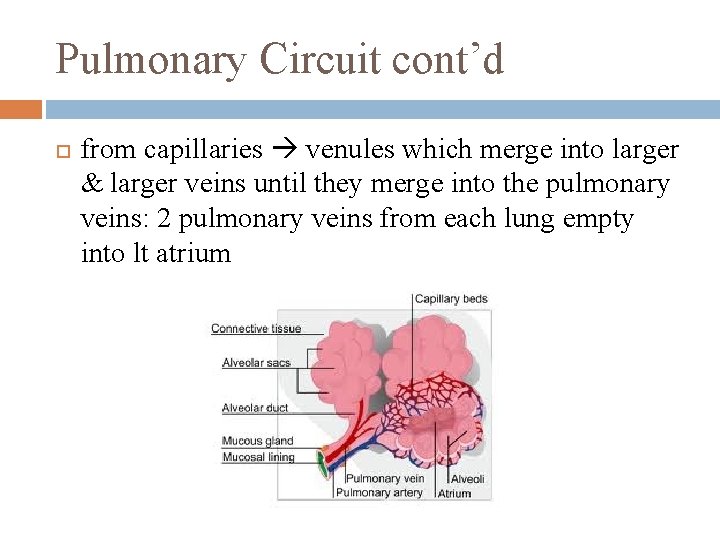

Pulmonary Circuit cont’d from capillaries venules which merge into larger & larger veins until they merge into the pulmonary veins: 2 pulmonary veins from each lung empty into lt atrium